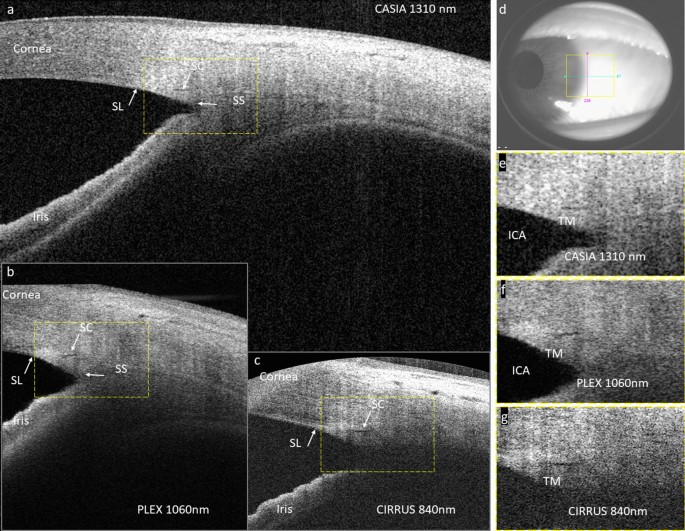

Figure 1 offers a visual comparison between SC images acquired on the same quadrant of one healthy eye from the three devices. The contrast of SC was seen best in CIRRUS compared to PLEX and CASIA images. The sharpness of PLEX image was lower compared to CIRRUS and CASIA images because it was an average of four images acquired at the same location without motion compensation. The penetration depth in tissue was seen shallowest in CIRRUS and deepest in CASIA. Deep tissue features such as scleral spur and iridocorneal angle were delineated in both PLEX and CASIA but not in CIRRUS. Moreover, the shadowing effect, while strongest in CIRRUS, was most alleviated in CASIA.

(a)–(c) Selected OCT B-scans of SC obtained by CASIA, PLEX, and CIRRUS, respectively, taken at the same quadrant of the same eye. The regions-of-interest (ROIs) of Schlemm’s canal are marked by yellow dashed rectangles. (d) White-light camera image showing the acquisition location. (e)–(g) Zoom-in views of the SC ROIs in CASIA, PLEX, and CIRRUS images, respectively. ICA: iridocorneal angle; SC: Schlemm’s canal; SL: Schwalbe’s line; SS: scleral spur; TM: trabecular meshwork.

The performance metrics were designed to assess the discernability of SC from the OCT devices: contrast measures the local SNR of the SC in each image; coverage is a measure to assess the portion of SC that can be successfully visualized within an OCT volume; continuity shows how well the continuous variation in SC size was captured by each device. CIRRUS offered the best 3D visualization performance in terms of contrast and coverage. The contrast advantage of CIRRUS can be attributed to the higher sensitivity, the stronger backscattering, as well as the superior optical resolution associated with the shorter wavelength. The coverage and continuity will be affected by not only the aforementioned factors but also the scan speed and sampling density in the slow scan direction. It can be seen from the results that none of them offered 100% continuous coverage of SC within one volume although SC was supposed to remain open in healthy eyes. It illustrates the challenges of SC visualization using OCT, which include 1) shadowing obscureness from the superficial tissues like epi- and intra- scleral blood vessels and the conjunctiva; 2) deterioration from eye movement under slow volumetric scan speed; 3) reduced SNR and insufficient resolution at the iridocorneal recess where SC resides. As seen in Fig. 1, although CIRRUS provided the highest contrast of SC, it has the lowest signal penetration in tissue and deep tissue features, such as scleral spur and iridocorneal angle, which cannot be fully delineated. Moreover, the shadowing effect was most severe in CIRRUS. These factors make the identification of SC more difficult in CIRRUS images. Conversely, PLEX and CASIA were able to delineate most of the key anatomical features needed to identify the SC, while manifesting less shadowing effect compared to CIRRUS. This observation demonstrates the benefit of adopting longer wavelengths in SC imaging. In terms of suppression of eye movement, PLEX was supposed to outperform the other two devices with an A-scan speed three times higher than that of CIRRUS and CASIA. Nevertheless, PLEX only employs OCT-A protocols where each structural OCT B-scan is a result of averaging several repeated B-scans taken at one slow-scan location. Considering that the size of SC may be changing over time to produce a pulsatile flow and eye motion is not compensated during image acquisition, this averaging process may wash out details of SC, leading to a reduced contrast as well as less coverage and continuity in SC visualization, and undermining the advantage brought by the scan speed. We recently investigated a mega-Hertz SS-OCT device at 1060 nm for SC visualization and showed that it was possible to suppress the motion artifact when the volumetric acquisition was done within one second30. We also found full coverage of SC within a single volume and successfully segmented the SC from each of the B-scans. These results suggested that, although the SNR plays an important role in the delineation of SC, the acquisition speed as well as motion suppression seem to have major impacts on SC visualization in general31. It would be beneficial for studies of SC provided that more flexibility is offered by the manufacturer in terms of image acquisition protocols.